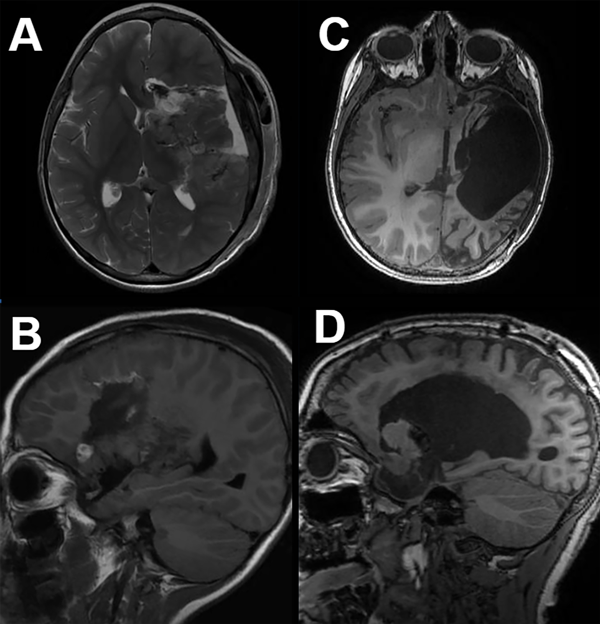

Figura 4. Imágenes de RM axial (superior) y sagital (inferior) de hemisferotomia funcional (A y B) y hemisferotomía lateral modificada (C y D). A y B: HF: se utiliza una ventana perisilviana transcortical para exponer el ventrículo lateral, y a través de esta abertura se realiza una callosotomía transventricular parasagital del cuerpo. El resto de la corteza frontal y posterior está desconectado del tálamo ipsilateral, pero se conservan las estructuras más profundas y la ACM. La craneotomía necesaria se extiende hasta la sutura sagital de la línea media. C y D: la HPI modificada extrae un bloque de tejido que incluye el opérculo frontotemporoparietal y las estructuras profundas subyacentes. La corteza frontal y posterior restante está desconectada del tálamo ipsilateral y del hemisferio cerebral contralateral.